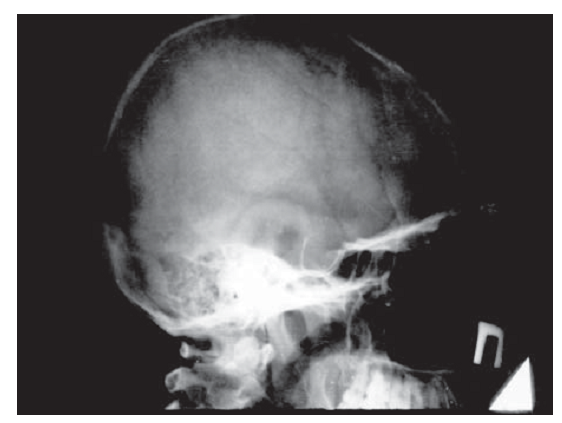

Гипофиздің интраселлярлы ісіктерінің рентгендиагностикасы түрік ершігінің өлшемдерін анықтауға негізделеді. Қалыпты жағдайда түрік ершігінің өлшемдері тең: сагиттальды — 12–15 мм, вертикальды— 8–9 мм (2.2 сурет).

2.2 сурет. Рентгенкраниография:

а — түрік ершігінің рентгенографиялық бағдарлары;

б — қалыпты жағдайдағы түрік ершігінің рентгенограммасы

Гипофиздің үлкен аденомалары түрік ершігі өлшемдерінің үлғаюына, кіреберісінің кеңеюіне, сына тәрізді сүйек өсінділерінің жіңішкеріп, қысқаруына, түбінің тереңдеуіне, ершік арқасының бұзылуына, екі контурлы болуына (бір немесе екі кескіннің нақты болмауы) әкеледі, дегенмен бұл ешқандай диагностикалық қиындықтар тудырмайды (2.3 сурет). Түрік ершігінің шекарасынан аспайтын гипофиз микроаденомаларының рентгенограммаларында ешқандай өзгерістер анықталмайды.

Сурет 2.3. Гипофиз макроаденомасы кезіндегі бассүйек рентгенограммасы